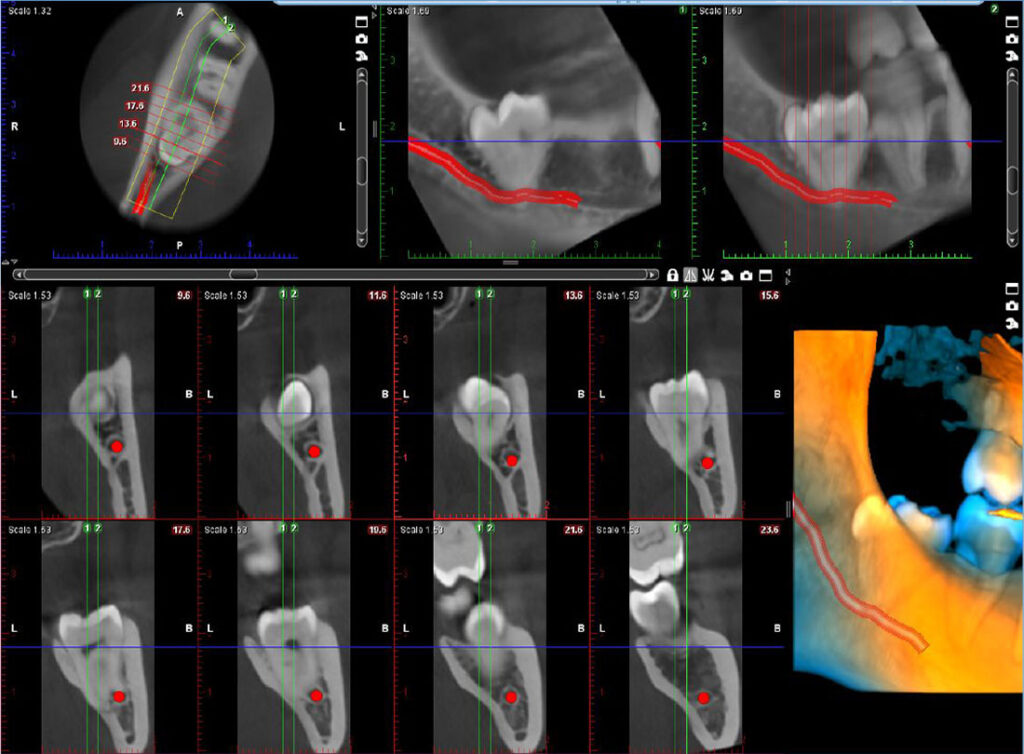

06. Implant plan

07. Alatka za formiranje regije

• Vizuelizacija impaktiranih zuba

• Procena položaja neizniklih zuba

• Identifikacija resorpcije korena

• Vizuelizacija prekobrojnih zuba

Primena CBCT snimka u oblasti:

Maksilofacijalna Hirurgija

Oralna Hirurgija

Implantologija